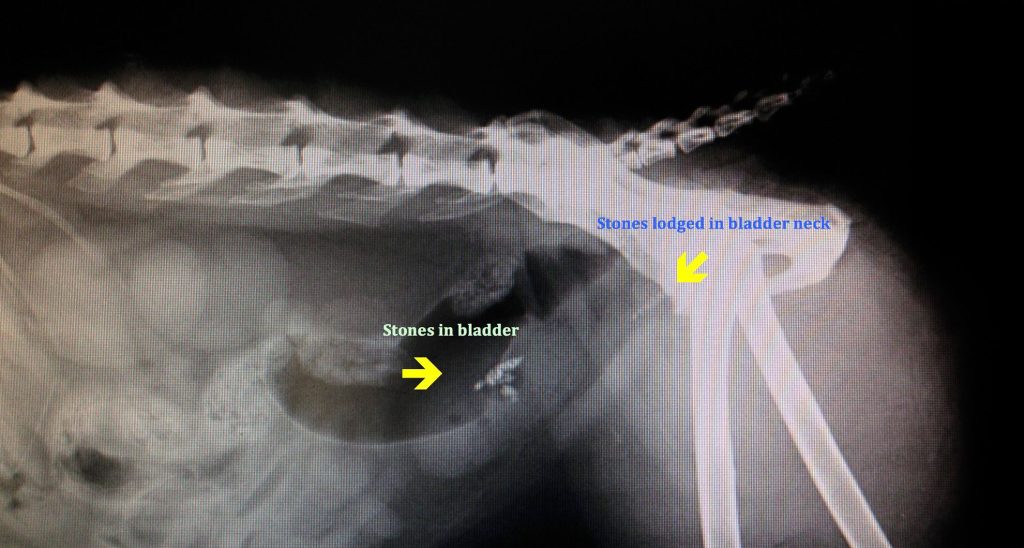

檢查階段

獸醫通常會先進行以下檢查:

- X 光檢查:確認結石大小、位置及數量。

- 超音波:偵測 X 光難以發現的小結石,評估泌尿道及膀胱狀況。

臨床檢查:X光下有一結石影像,超音波下也有結石影像。PH7.5,鏡下可見struvite結晶 。